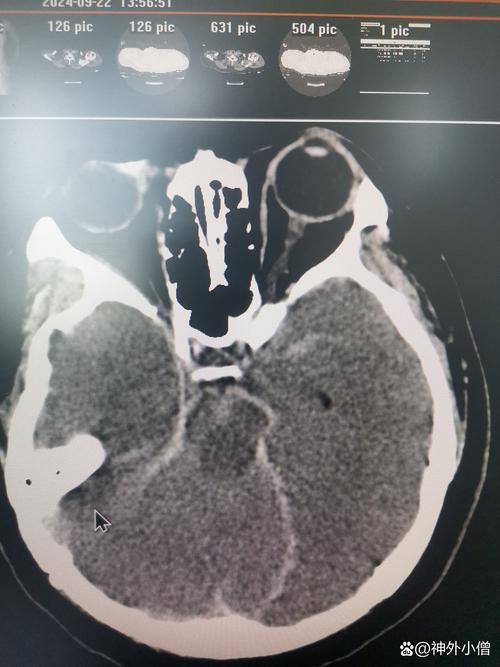

CT检查如何诊断术后出血?(影像学表现)

CT是诊断脑出血的“金标准”,快速、准确,对于脑梗术后患者,CT检查主要看以下几点:

典型CT表现:高密度影

- 急性期出血(数小时内): 在CT图像上,新鲜的出血表现为边界清晰的、密度增高的区域(白色或亮白色),这与脑梗死的低密度(黑色或暗色)影形成鲜明对比。

- 位置: 血肿可以位于:

- 手术区域(原发): 最常见,即在开颅的部位或血肿清除的部位再次出现新的高密度影。

- 远离手术区域(继发): 可能是由于再灌注损伤导致梗死区内部出血,或因高血压导致其他部位血管破裂。

周边水肿效应

- 出血灶周围通常会有一圈低密度(黑色)的水肿带,这是血液成分刺激脑组织引起的炎性反应和细胞毒性水肿,水肿范围越大,占位效应越明显。

占位效应与中线移位

- 这是评估出血严重程度的关键指标。

- 占位效应: 血肿和周围水肿会挤压、推移正常脑组织。

- 中线移位: 如果出血发生在大脑一侧,会推挤大脑镰(大脑中间的硬脑膜),在CT上可以看到中线结构(如脑室、脑沟)向对侧偏移,中线移位超过5mm通常被认为是比较严重的情况,需要紧急处理。

破入脑室系统

- 如果出血量大或靠近脑室,血液可能破入脑室,导致脑室内出现高密度影,这会堵塞脑脊液循环通路,引起急性脑积水,使病情急剧恶化。